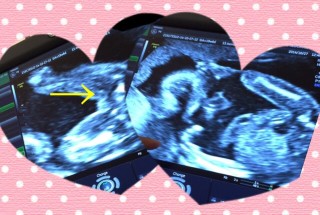

19w0dで性別判明しました!

待望の男の子でした^^

エコー画像の→があるあたりがタマタマやおちんちんだそうです☆

推定体重252グラムでした♪